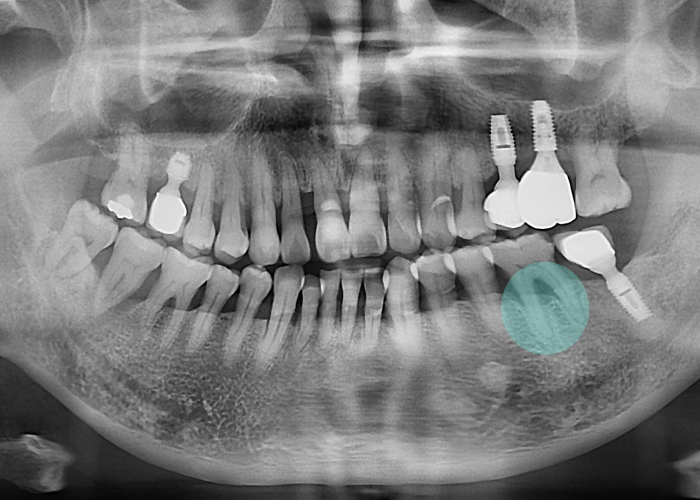

이를 빼지 않고

4년 경과후 엑스레이 사진입니다.

뿌리 끝까지 뼈가 사라지고

주변 신경과도 가까워져

수술 난이도가 매우 높아지는거죠.

이런 경우

할 수 있는 치료 옵션이 줄어들고

환자의 불편과 치료 기간은

훨씬 길어질 수밖에 없습니다.